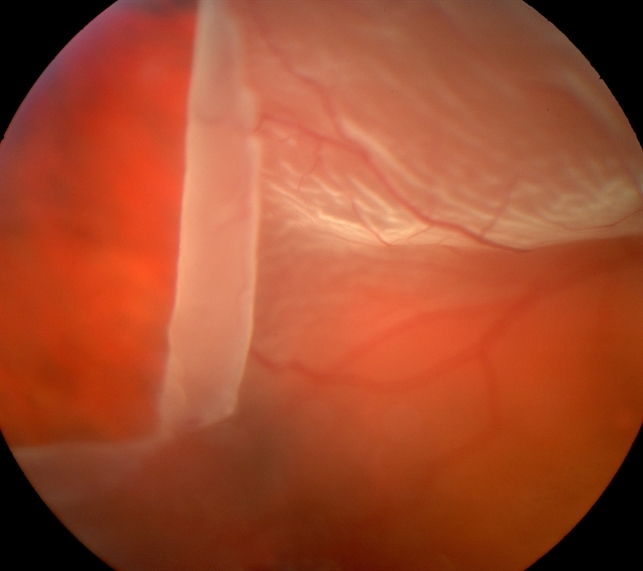

Фото

Диагностика